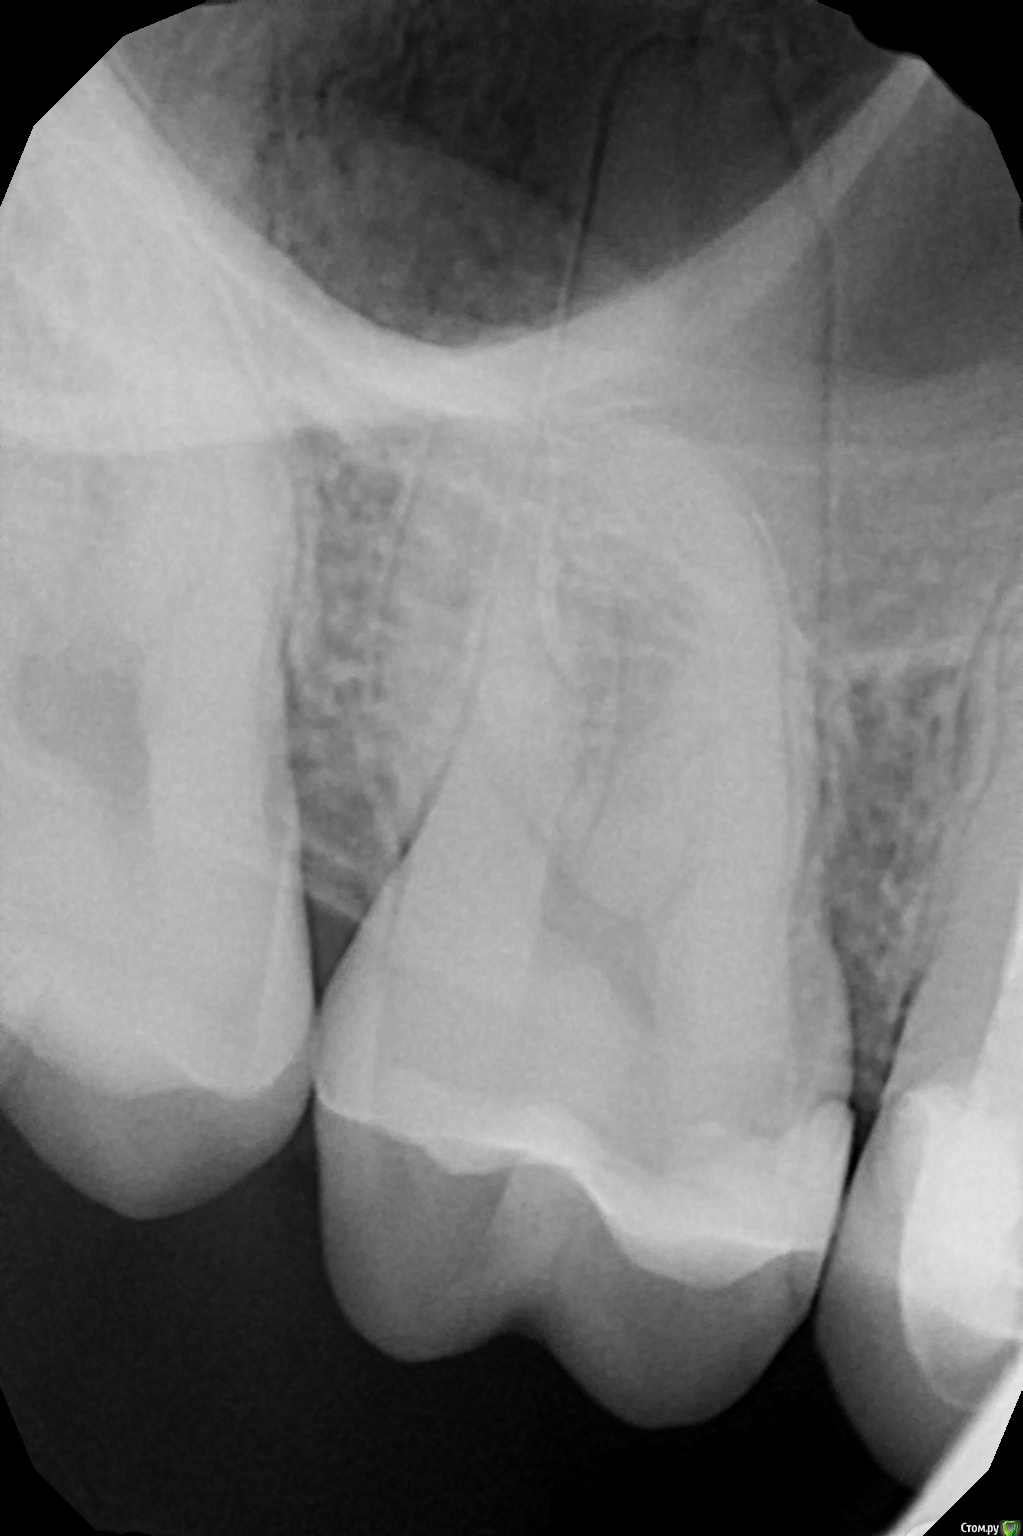

GrrGrrr Опубликовано 17 сентября, 2016 Поделиться Опубликовано 17 сентября, 2016 Проблема с 16 зубом.Устанавливал коронку на 15-ый зуб. Ортопед сказал, что необходимо вначале вылечить небольшой кариес на соседнем 16-ом зубе. На приёме у терапевта в конце лечения, при накусывании бумаги пломба "хрустнула", из-за чего доктору пришлось что-то переделывать. После лечения (которое было 7 августа) зуб болит при попадании твёрдой пищи, при сильном надавливании ногтем или зубочисткой и т.д. Причём вначале боль была вдоль всей бороздки, сильнее ближе к 15-ому зубу. После этого хотел к этому доктору на шлифовку и ещё один раз на частичную замену пломбы. Зуб болеть стал меньше, теперь только при сильном надавливании ближе к 15-ому зубу. Вначале динамики между посещениями не было никакой, но последние несколько дней ощущения, что болеть стало меньше, но до конца боль так и не прошла.Судя по снимку, можно ли сделать вывод, что это нормально или, может быть, есть какие-то проблемы? Ссылка на комментарий

anvladd Опубликовано 18 сентября, 2016 Поделиться Опубликовано 18 сентября, 2016 Щель между пломой и зубом со стороны 15. Переделать! Ссылка на комментарий